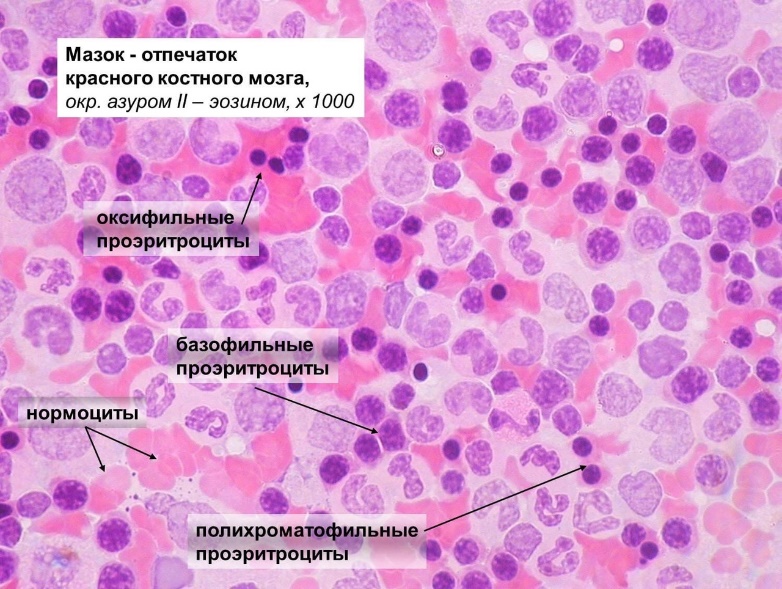

Изучение костного мозга: анатомия и функции